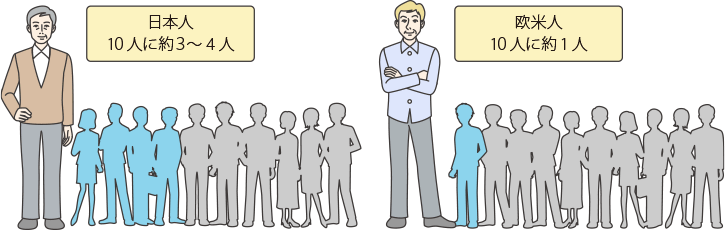

肺がんにはいくつかの種類がありますが、がんの種類では、扁平上皮がんなどに比べて腺がんが増えています。また、世界的な動向をみると、肺がんになる確率は、欧米人と比べて日本人のほうが低い傾向があることがわかっています。

EGFR遺伝子変異は、欧米人よりも日本人の非小細胞肺がんの患者さんに多く、全体の30〜40%に認められます。

変異の中にはEGFRのスイッチを常時ONにして、がん細胞の増殖を促すものもあります。

EGFR遺伝子変異は、日本人の非小細胞肺がんの患者さん全体の30〜40%に認められます。欧米人よりも日本人などのアジア系の人種、男性よりも女性、タバコを吸う人よりも吸わない人に多く、非小細胞肺がんの中でも腺がんの患者さんに多いことなどがわかっています。